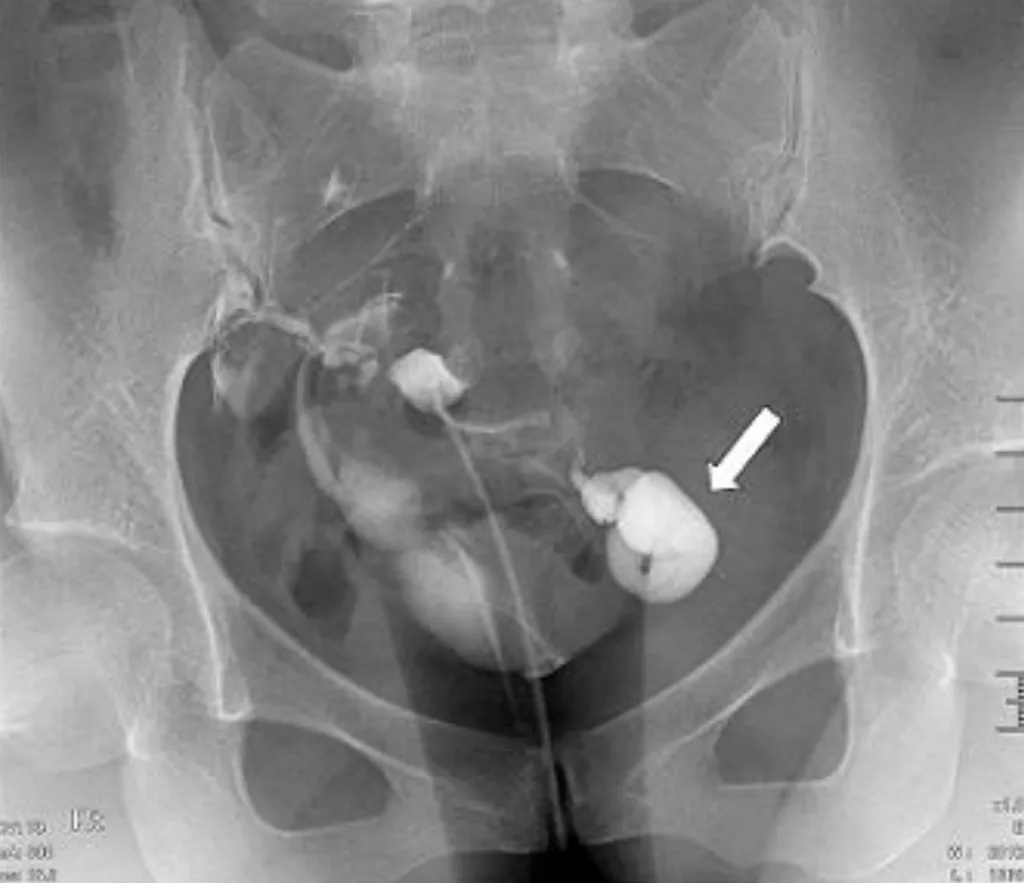

【114-2 醫學(六) 第73題】34 歲女性子宮輸卵管攝影檢查呈現如圖,箭號所指之病灶,下列何者為最恰當之診斷?

詳解

破題關鍵

這張子宮輸卵管攝影(HSG)顯示左側輸卵管末端呈現明顯的囊狀擴張,且顯影劑無法溢流到腹腔,這是典型的輸卵管積水影像。

選項拆解